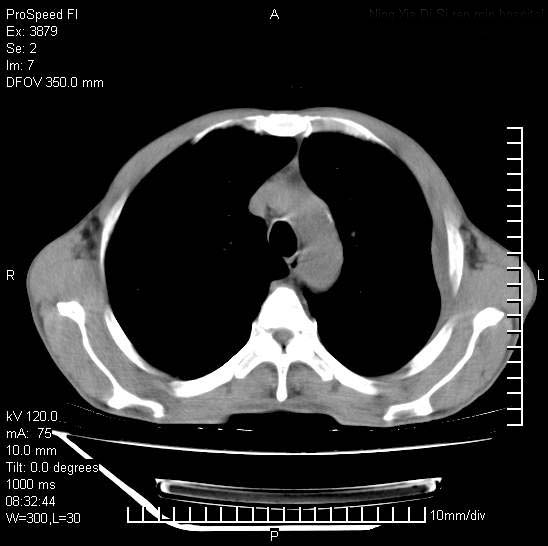

以下是引用37度在2008-6-6 11:20:00的发言:[br]1.包裹性积液,多考虑结核性;[br]2.穿刺术后改变。

以下是引用312nanyang在2008-6-6 15:12:00的发言:[br]基本支持楼主意见[br]疑问?左下肺支气管旁的软组织(16层)密度怎么解释?淋巴结还是斜裂胸膜增厚所致?能否增强进一步检查